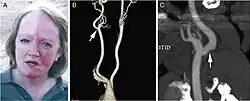

Das Harlequin-Syndrom ist eine Störung des vegetativen Nervensystems mit einseitiger Hautrötung und Schwitzen meist nur im Gesicht, mitunter auch am Arm oder Brustkorb. Die Erkrankung kann in jedem Alter auftreten, häufig in warmer Umgebung oder bei Belastungen.[1]

Klinische Erscheinungen

Klinische Kriterien sind:[1][2]

- Einseitige Hautrötung und kompensatorisches Schwitzen, auf der Gegenseite Anhidrose

- Normale Sympathikus-Innervation des Auges

- Mitunter parasympathische Störung der Augenbewegung